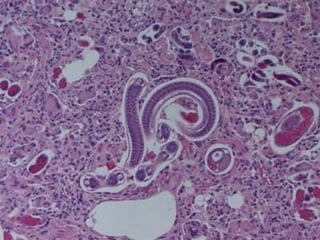

Parasitism One organism lives on or inside another organism and harms it (+/-) Endoparasitism Ectoparasitim Parasitoidism Usually large and multicellular Parasite obtains all or part of its nutrients from the other organism Host Organism that is harmed in relation ship; the one that provides the nutrients to the parasite Parasite Organism that gets its nutrients from the host Do they want to kill their host? No, because they need them…mostly annoying

Parasitism One organismlives on or inside another organism and harms it (+/-) Endoparasitism Ectoparasitim Parasitoidism Usually large and multicellular Parasite obtains all or part of its nutrients from the other organism Host Organism that is harmed in relation ship; the one that provides the nutrients to the parasite Parasite Organism that gets its nutrients from the host Do they want to kill their host? No, because they need them…mostly annoying